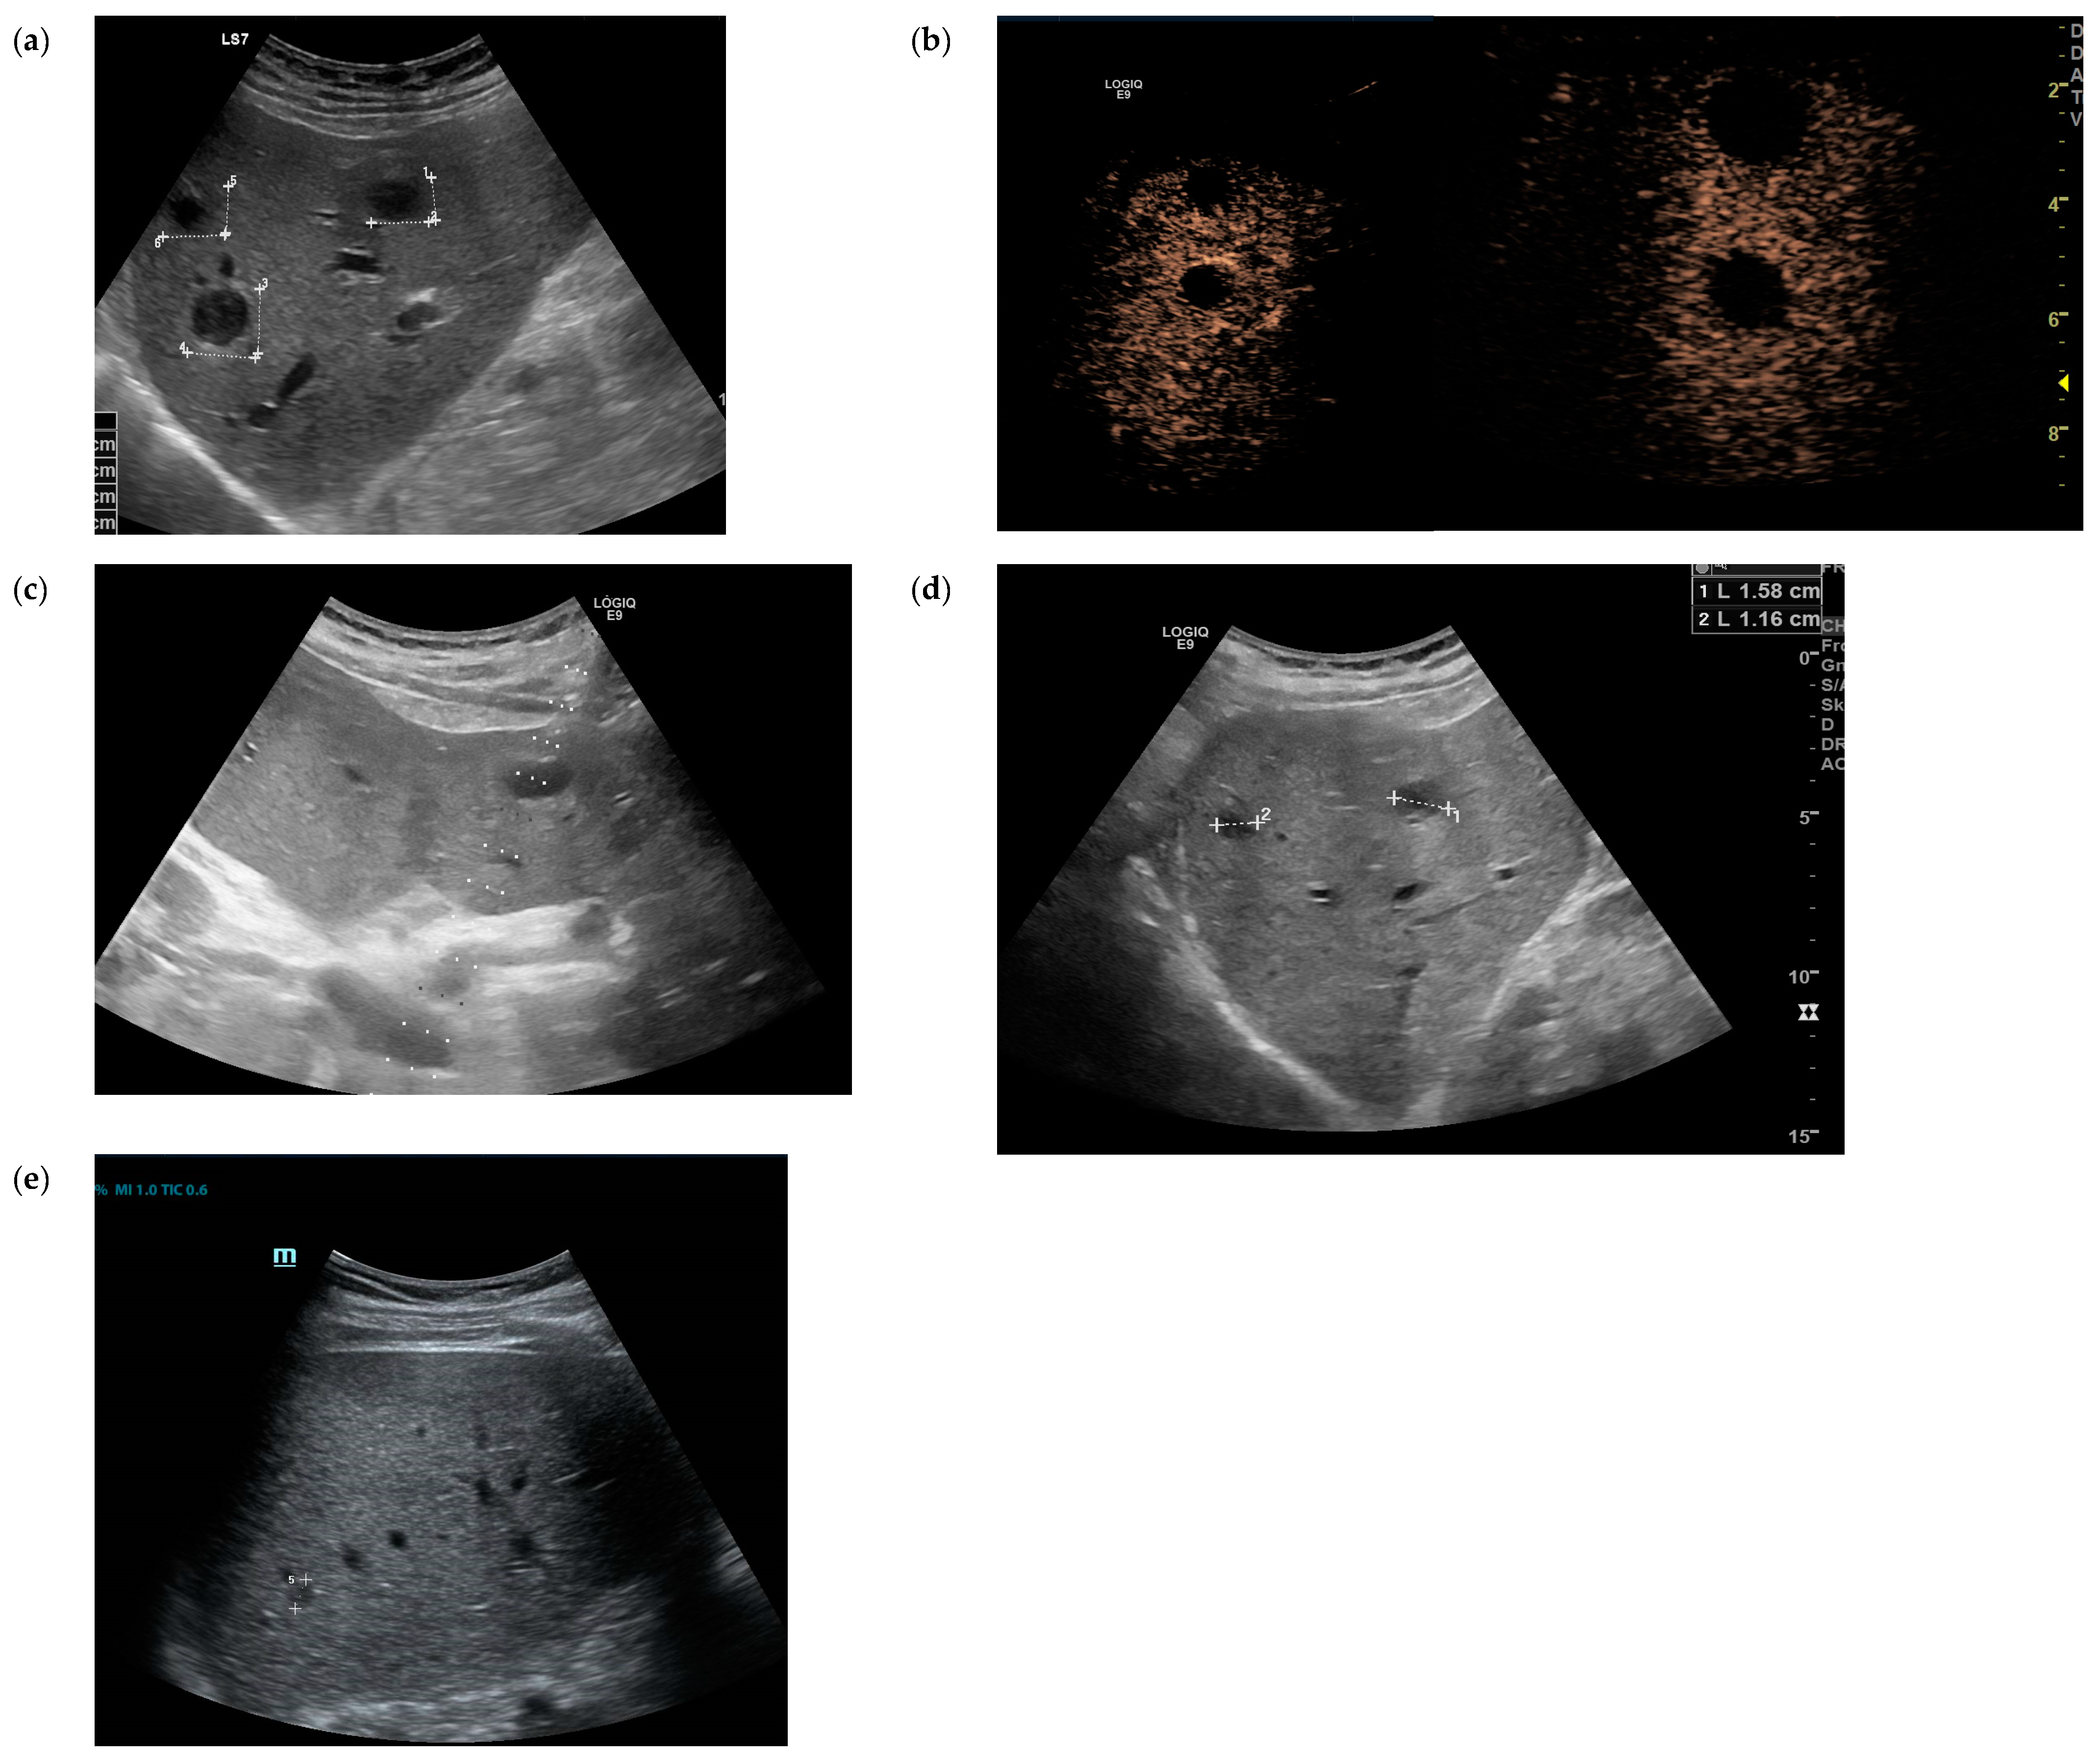

2. Case Presentation